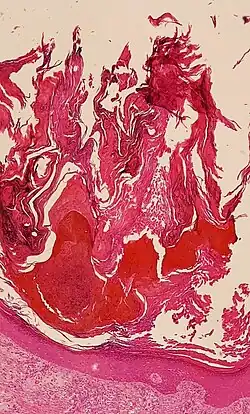

| Micrograph showing prominent hyperkeratosis in skin without atypia. H&E stain. | |

Hyperkeratosis is thickening of the stratum corneum (the outermost layer of the epidermis, or skin), often associated with the presence of an abnormal quantity of keratin,[1] and is usually accompanied by an increase in the granular layer. As the corneum layer normally varies greatly in thickness in different sites, some experience is needed to assess minor degrees of hyperkeratosis.